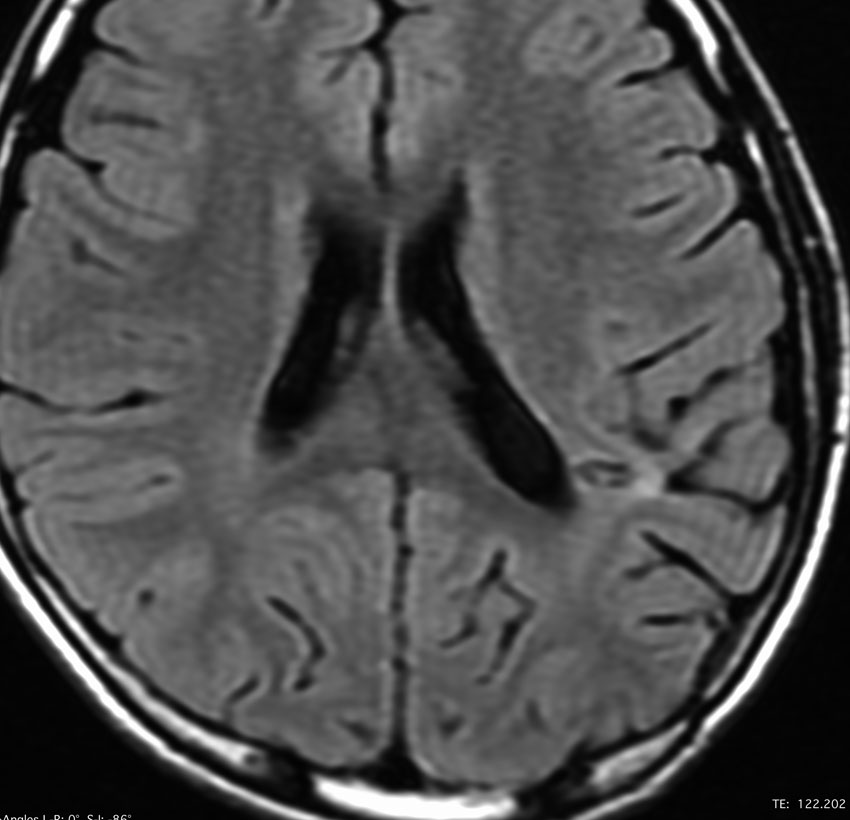

10代の少女に見つかったDNTです。難治性のてんかんがあり1日になんども意識減損を生じて,けいれんを止める薬をたくさん飲んでいて副作用のために眠気で日常生活が困難でした。でも,他の症状は何もありませんでした。左の頭頂葉と側頭葉と後頭葉の境目にできたものです。おそらくお母さんのお腹の中いたときからあった腫瘍なので何もしないで様子を見てもいいのです。でも,てんかん発作がひどいので腫瘍だけを摘出しました。DNTだけを取っても後遺症が残ることはほとんどありません。この場所は周囲の脳組織をとると後遺症がでる場所 (eroquent area)なので,てんかんを止める目的でもかなりの理由がないと周囲の脳組織は摘出しません。この子は,抗てんかん薬もいらなくなって完治しました。